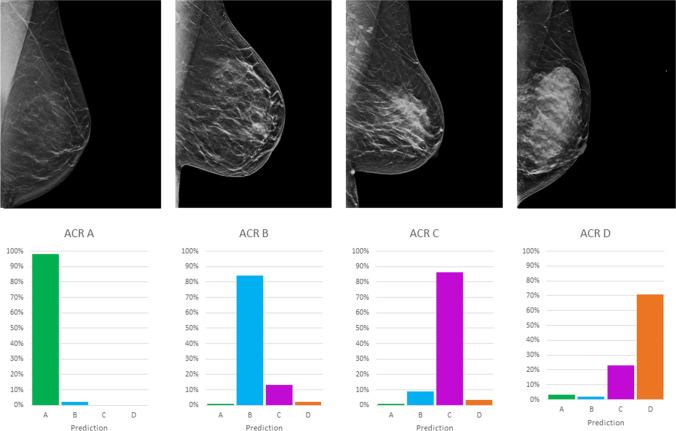

In total, 4605 synthetic 2D images (1665 patients, age: 57 ± 37 years) were labeled according to the ACR (American College of Radiology) density (A-D). Two DCNNs with 11 convolutional layers and 3 fully connected layers each, were trained with 70% of the data, whereas 20% was used for validation. The remaining 10% were used as a separate test dataset with 460 images (380 patients). All mammograms in the test dataset were read blinded by two radiologists (reader 1 with two and reader 2 with 11 years of dedicated mammographic experience in breast imaging), and the consensus was formed as the reference standard. The inter- and intra-reader reliabilities were assessed by calculating Cohen's kappa coefficients, and diagnostic accuracy measures of automated classification were evaluated.

The two models for MLO and CC projections had a mean sensitivity of 80.4% (95%-CI 72.2-86.9), a specificity of 89.3% (95%-CI 85.4-92.3), and an accuracy of 89.6% (95%-CI 88.1-90.9) in the differentiation between ACR A/B and ACR C/D. DCNN versus human and inter-reader agreement were both "substantial" (Cohen's kappa: 0.61 versus 0.63).